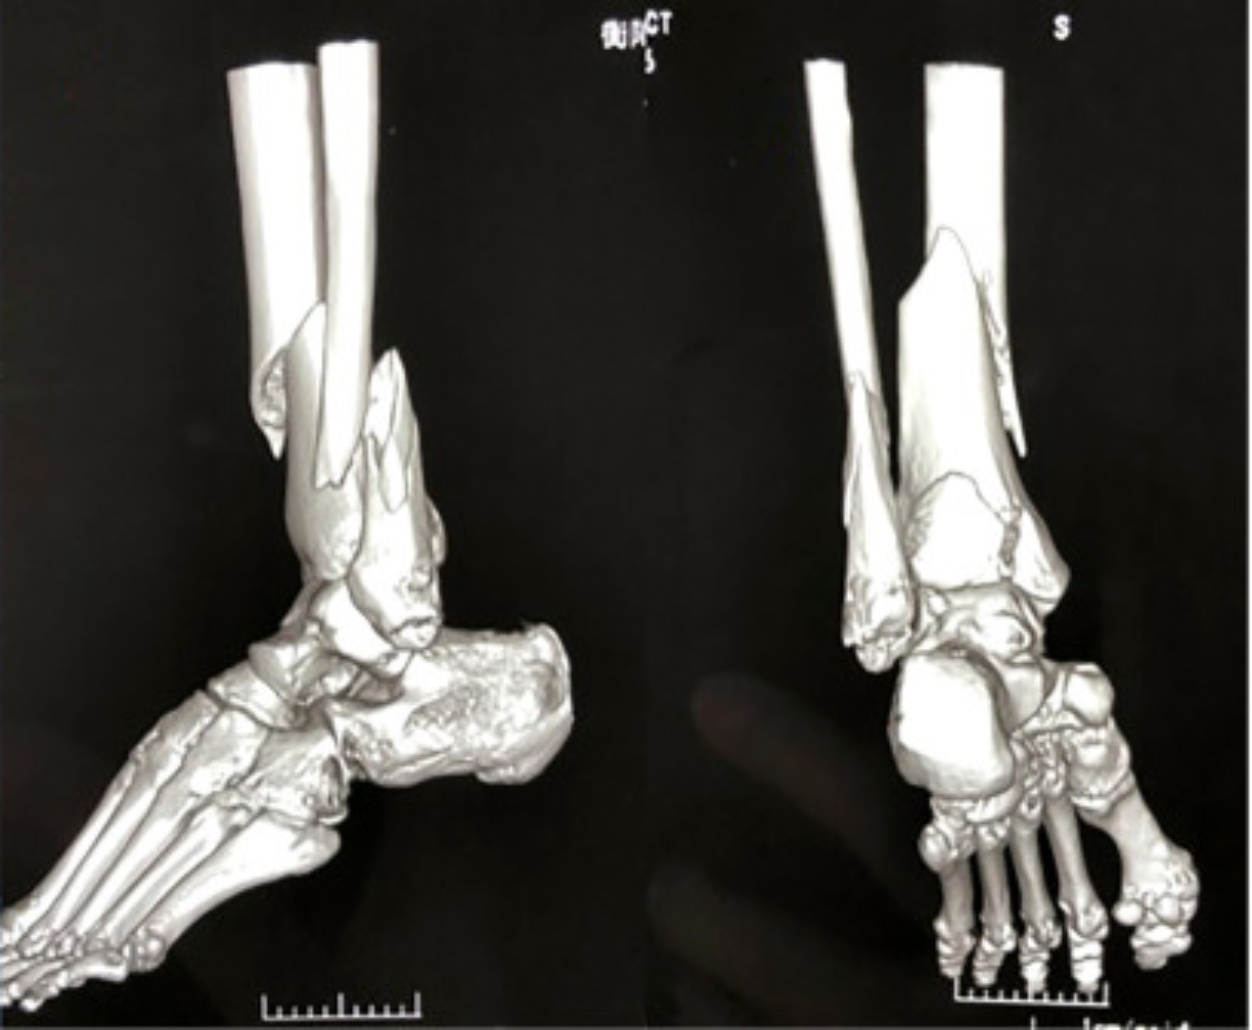

因此,医生们逐渐开始分阶段治疗Pilon骨折(见图1)。一期通过跟骨牵引、外固定架暂时固定Pilon骨折(见图2),恢复肢体长度和力线,避免早期切开加重软组织损伤(如伤口感染、皮瓣坏死等),开放性骨折或感染风险高的还可联合应用VSD;待软组织恢复后,二期再行骨折的解剖复位和接骨板固定(见图3) [5]。研究显示,通过分阶段治疗,并发症率从传统治疗的40%降至10%~15%,延期手术组的功能恢复优良率(85%)显著高于早期手术组(65%) [5]

Figure 1. Pilon fracture

1. Pilon骨折

Figure 2. External fixation

2. 外支架固定

Figure 3. Internal fixation

3. 内固定